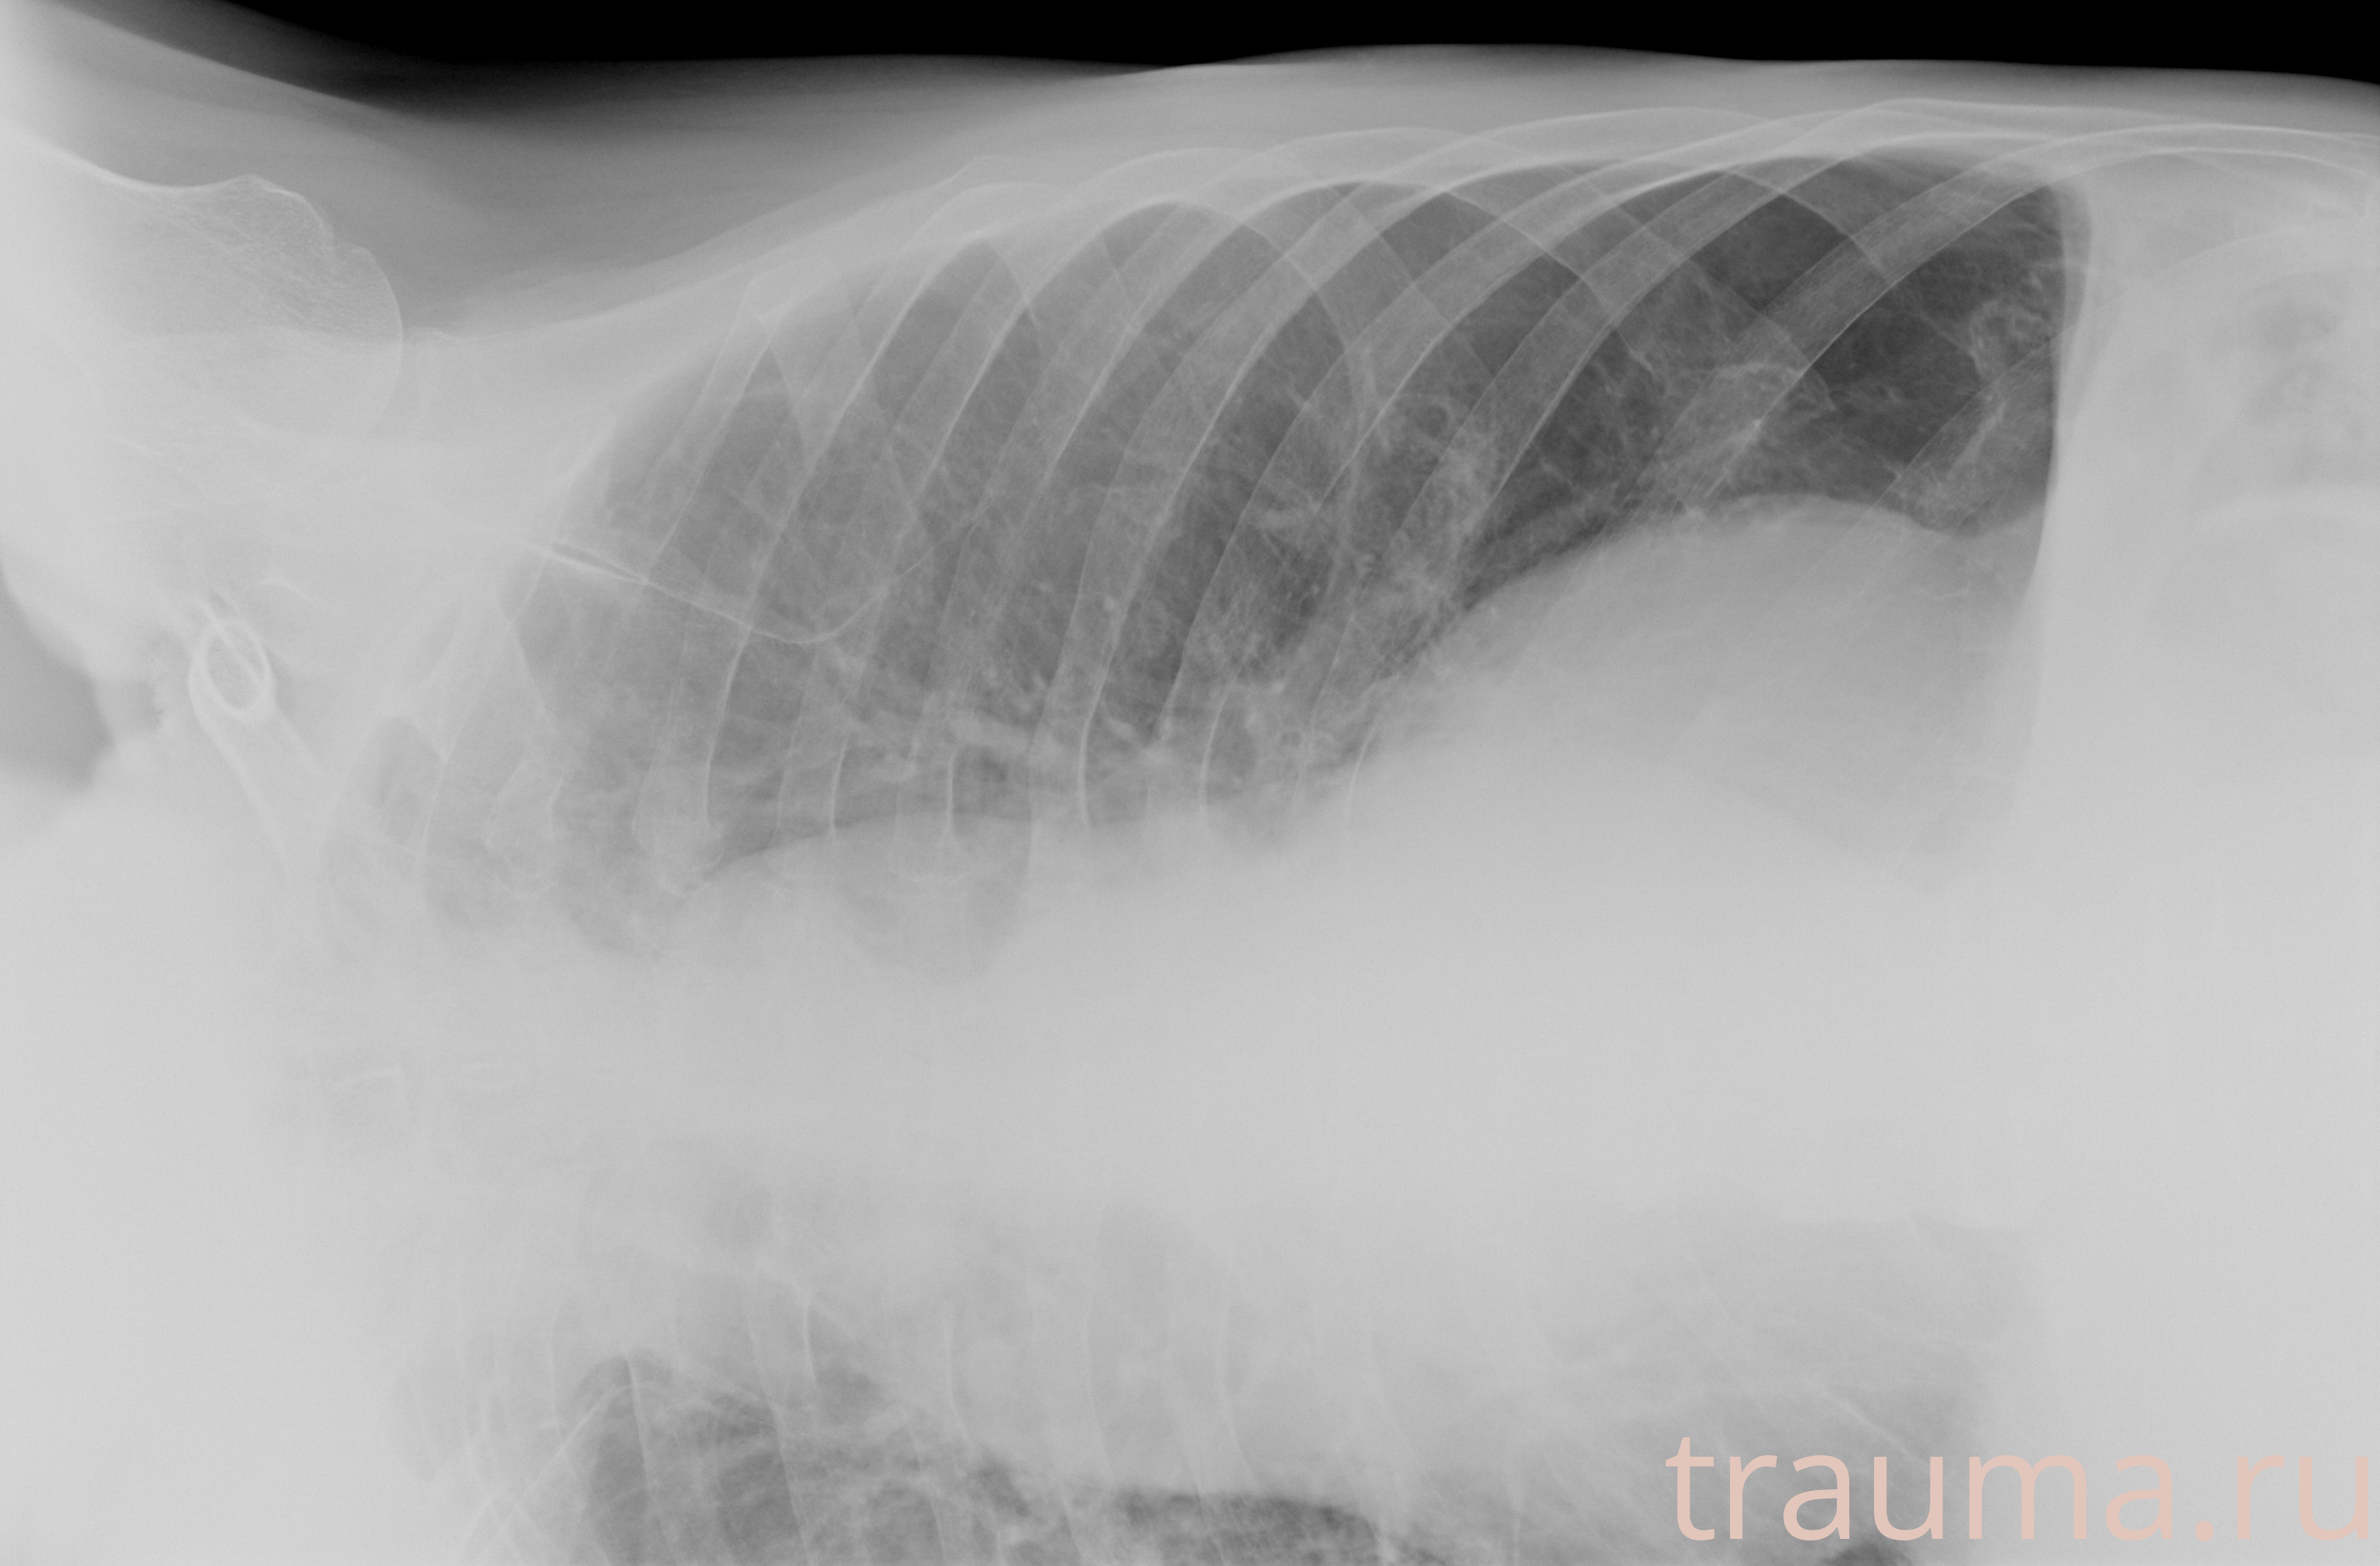

Рентген на дому: по вашему адресу приезжает врач-рентгенолог, травматолог-ортопед с мобильным рентгеновским аппаратом, проводит диагностику травмы или заболевания, делает необходимые рентгенограммы, дает рекомендации по дальнейшему лечению. Получить качественные снимки в домашних условиях возможно благодаря уникальной методике, разработанной МосРентген Центром для института  Склифосовского

при переломе шейки бедра и пневмонии от компании МосРентген Центр - партнера Института имени Склифосовского